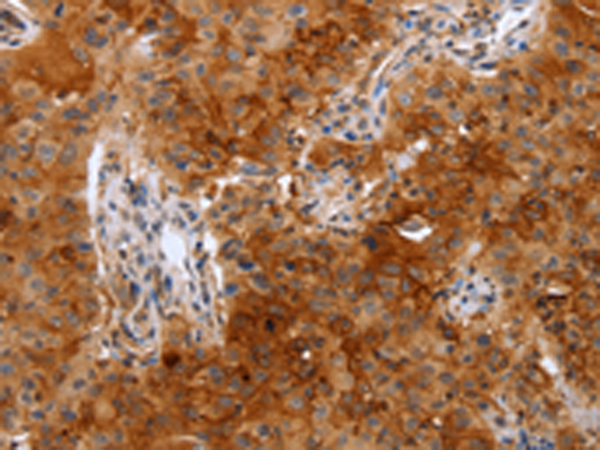

分类: 科研抗体货号: P07571别名: PDS; PGD2; PGDS; LPGDS; PGDS2; L-PGDS应用: WB,IHC反应种属: Human, Mouse